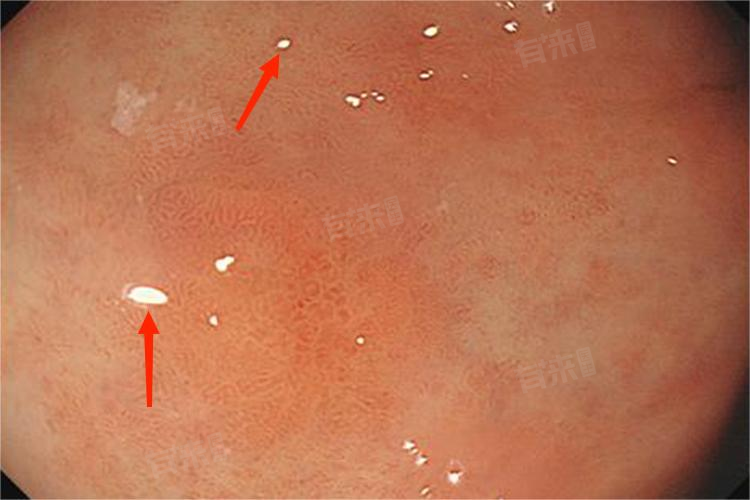

1、胃镜检查及活检:胃镜能直观观察胃黏膜形态,发现黏膜色泽改变、粗糙不平、颗粒状等可疑肠化区域。在可疑部位取组织进行病理活检,通过显微镜观察细胞形态,确定是否存在肠化及肠化的类型、程度,为后续治疗提供关键依据。